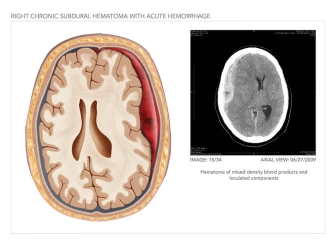

Brain Surgery and Skull Reconstruction